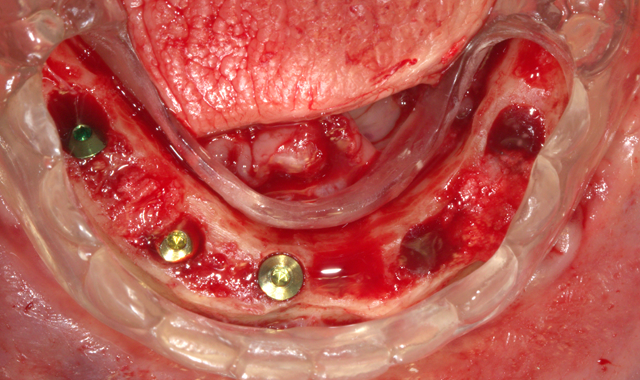

A full thickness flap was performed, as well as extraction of remaining mandibular teeth with alveoloplasty to create restorative space and achieve an even ridge. A clear duplicate surgical guide was used for implant position and distribution. Five BioHorizons Tapered Internal implants were placed using a second stage approach (Fig. 3).

After an uneventful healing period, uncovery of the implants was performed and multi-unit abutments were placed and torqued to 30NCM (Fig. 4).

Fig. 3

Fig. 4